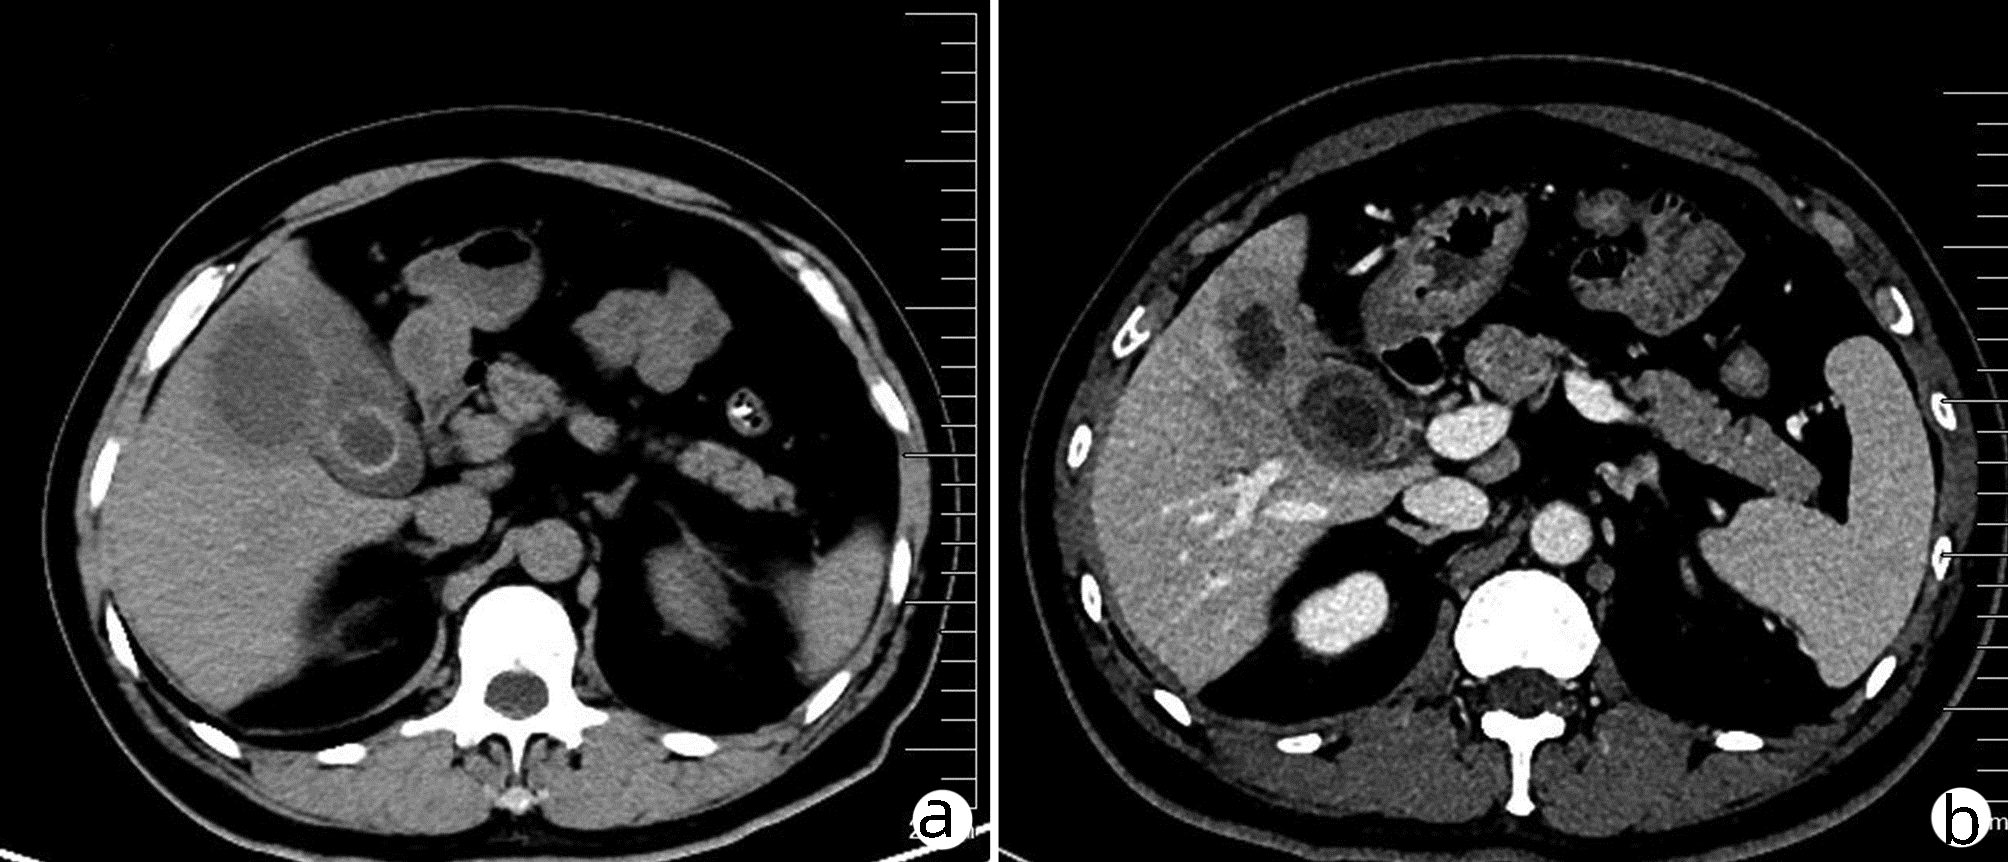

Liver abscess caused by type II gallbladder perforation: A report of 3 cases and literature review

Shaoxiong REN, Ze LIANG, Jingzhao HAN, Hongfang TUO, Yanhui PENG

2022, 38(4): 894-897. DOI: 10.3969/j.issn.1001-5256.2022.04.031

Abstract(1105) HTML (269) PDF (2784KB)(47)

Abstract: